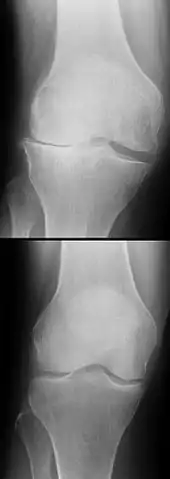

L'évolution à long terme du genou être commence à bien connue dans le cas des ligamentoplasties, faisant apparaitre un haut niveau de satisfaction subjective à plus de 20 ans chez la majorité des patients, une stabilité antéro-postérieure et rotatoire normale dans 90% des cas, mais aussi une augmentation de signes d'arthrose (concernant surtout les patients ayant eu des lésions cartilagineuses ou méniscales concomitantes), ainsi qu'une altération durable de la proprioception[130],[131]. En revanche, on ne dispose pas d'études à 10 ans ou plus ni pour les protocoles récents de cicatrisation avec attelle, ni pour les toutes dernières techniques de suture chirurgicale[102].

Dans les années 1970 à 1980, la limite d'âge pour les opérations de reconstruction du LCA se situait environ à 35 ans. Ceci était dû aux possibilités opératoires encore restreintes en raison de la difficulté d'approvisionnement en sang et des mauvaises perspectives de guérison des LC. Aujourd'hui, il n'y a plus de limite d'âge[166]. L'état du genou, les souhaits du patients et sa motivation sont les facteurs essentiels pour la décision d'opérer ou non. Dans la plupart des cas, du point de vue médical, il n'y a pas besoin d'intervention chirurgicale immédiate pour une rupture de LC. Une rupture récente n'est opérée dans l'idéal qu'après six à huit semaines de physiothérapie ou kinésithérapie. Le genou a alors normalement perdu complètement son épanchement articulaire[167]. Dans de nombreux cas, l'opération a lieu plusieurs mois, voire années après la rupture du LC. Par exemple, on la pratique quand une instabilité du genou d'abord faible conduit à des douleurs pour le patient[167]. Dans les pays scandinaves, Norvège, Danemark et Suède, les temps moyens entre la rupture et l'opération sont respectivement de 7, 9 et 10 mois[168], par contre aux États-Unis c'est 2,4 mois. Les quartiles sont de 1,2 et 7,2 mois aux États-Unis, et de 4,2 et 17,8 mois en Norvège[37].

Certaines études plus récentes indiquent que dès six mois après une rupture de LC sans intervention opératoire, on peut observer des symptômes de dégénérescence des ménisques, si bien que les auteurs préconisent une reconstruction dans l'année suivant la blessure[169],[170],[171].